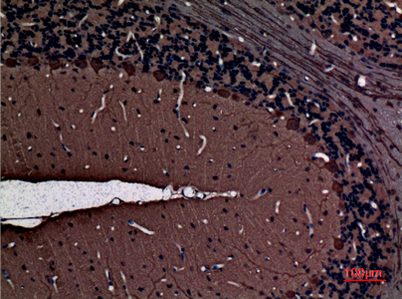

| Dilutions: | Western Blot: 1/500 - 1/2000. IHC-p: 1:100-300 ELISA: 1/20000. Not yet tested in other applications. |

| Background: | Protein kinase C (PKC) is a family of serine- and threonine-specific protein kinases that can be activated by calcium and second messenger diacylglycerol. PKC family members phosphorylate a wide variety of protein targets and are known to be involved in diverse cellular signaling pathways. PKC also serve as major receptors for phorbol esters, a class of tumor promoters. Each member of the PKC family has a specific expression profile and is believed to play distinct roles in cells. The protein encoded by this gene is one of the PKC family members. This protein kinase is expressed solely in the brain and spinal cord and its localization is restricted to neurons. It has been demonstrated that several neuronal functions, including long term potentiation (LTP) and long term depression (LTD), specifically require this kinase. Knockout studies in mice also suggest that this kinase may be involved in neurop |